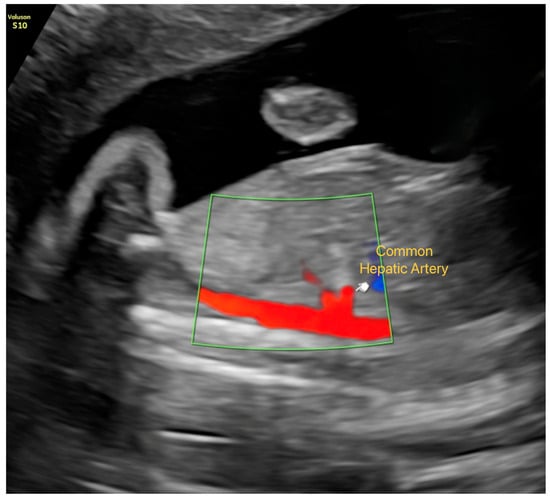

• Hepatic artery: The common hepatic artery was evaluated in a sagittal plane immediately distal to its origin from the celiac trunk, using the lowest possible angle of insonation. PI, RI, S/D ratio, and peak systolic velocity (PSV) were obtained (Figure 1).

Figure 1. Visualization of the Common Hepatic Artery in Late-Gestation Fetal Ultrasound. Color Doppler imaging showing the common hepatic artery in a sagittal plane immediately distal to its origin from the celiac trunk.